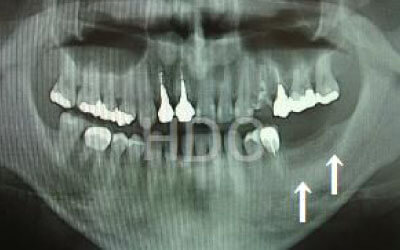

CTでは、骨や歯の状態を三次元で確認でき、正確な距離を測定することができます。

骨の厚さや傾き、神経の位置などを事前に詳しく計測することで、安全にインプラントを行うことができます。

骨が薄い場合、そのままインプラントを行うのはお勧めできません。

ただし、事前に骨を増やす治療を行ったり、インプラントと同時に骨を増やす治療をすることで、インプラントは可能です。

2 神経を傷つけるリスク

インプラントの手術では、顎の骨を通る神経を傷つけるリスクがあります。

しかし、事前にCTでしっかりと撮影し、三次元的に神経との距離を計測して治療計画を立てることで、心配は不要です。